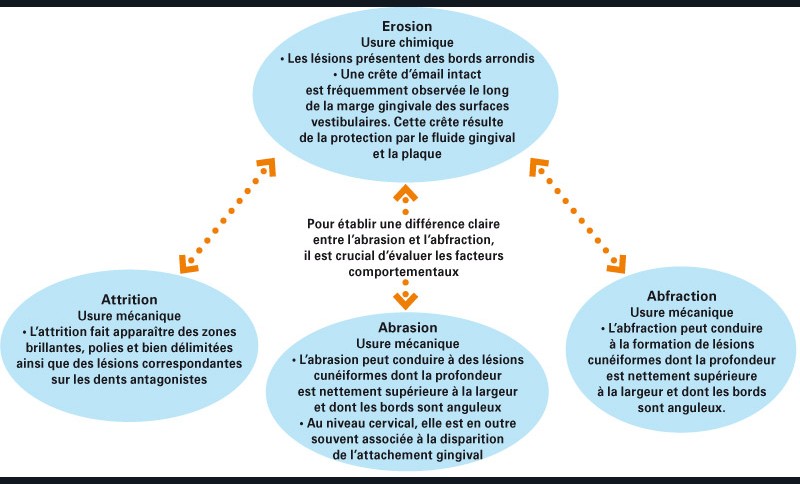

Plusieurs modes d’usure dentaire, dont l’érosion, peuvent être synchrones et interagir les uns avec les autres, ce qui rend le diagnostic clinique des érosions dentaires d’autant plus difficile(fig. 3 et 4).